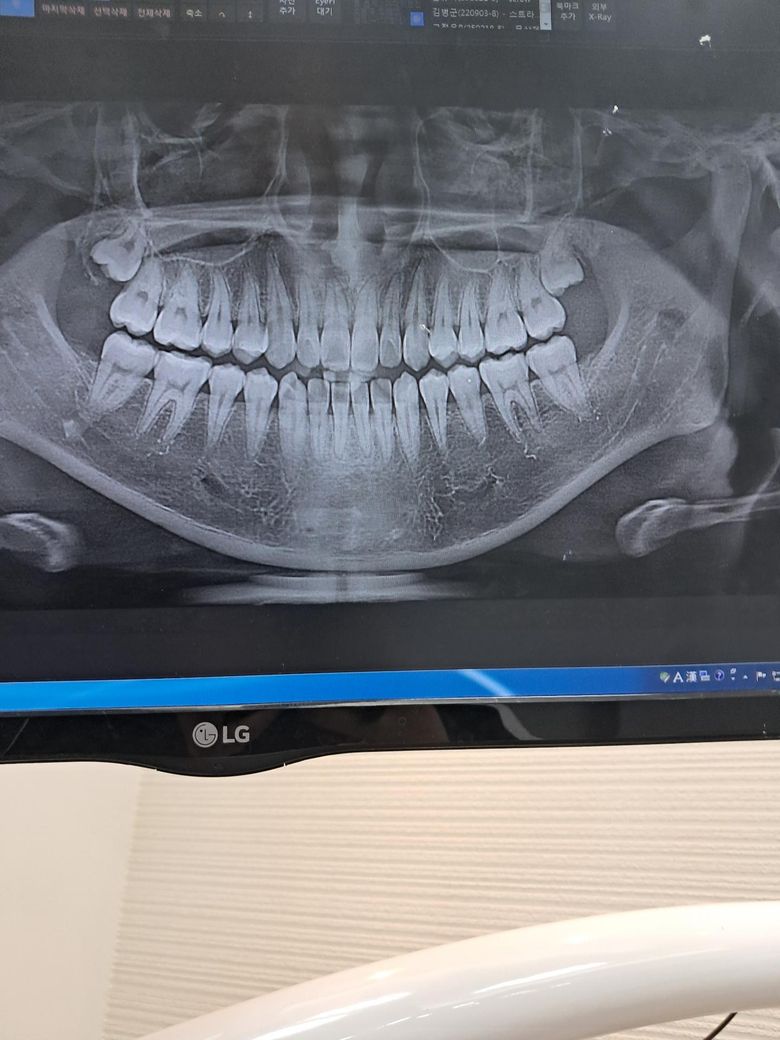

치과에서 정기검진 때 찍은걸로 갑자기 사랑니 상태가 궁금해져서 AI한테 물어봤는데 아래에 수평 매복 사랑니가 있다고 그러네요. 근데 제가 봤을 때는 없는 것 같아서 헷갈리기도 하고 질문 드려봅니다!

위에가 매복사랑니가 있고 아래는 없습니다 오른쪽 아래 골 경화상이 있는데 사랑니랑은 상관없고요 툭별히 문제가 있어보이진 않습니다